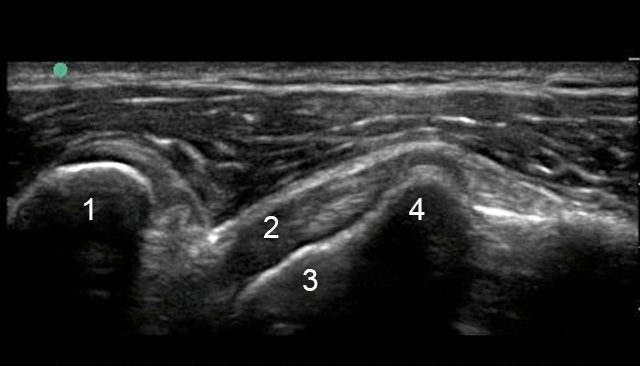

Imagen del tendón subescapular anterior del hombro

1. Apófisis coracoides

2. Tendón subescapular

3. Cabeza humeral

4. Tuberosidad menor